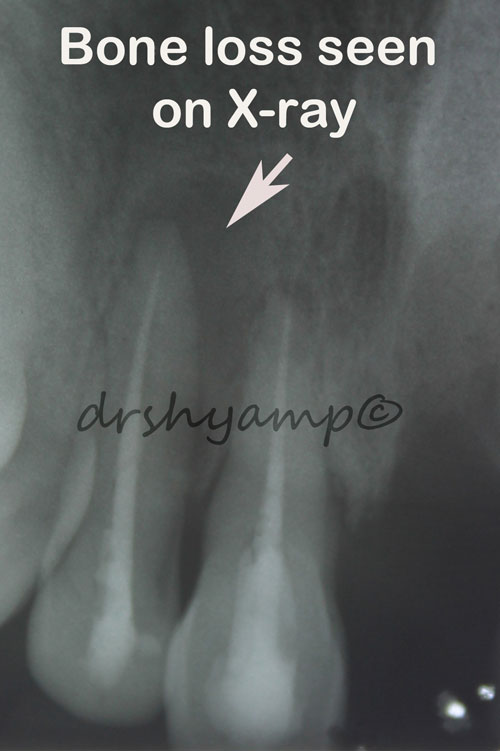

Periodontal flap surgery with bone grafting

Periodontal flap surgery with bone grafting

Periodontal flap surgery with bone grafting

Periodontal flap surgery with bone grafting

Periodontal flap surgery with bone grafting

Periodontal flap surgery with bone grafting

Periodontal flap surgery with bone grafting

Periodontal flap surgery with bone grafting

Periodontal flap surgery with bone grafting

Periodontal flap surgery with bone grafting

Periodontal flap surgery with bone grafting

Periodontal flap surgery with bone grafting

Periodontal flap surgery with bone grafting